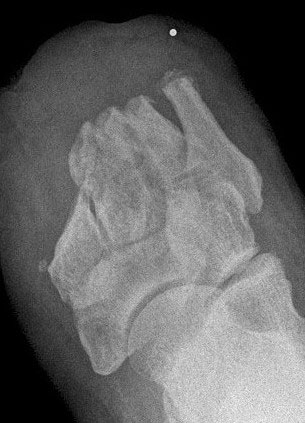

Das Ausmaß der Knochenresektion ergibt sich aus der Defektgröße bzw. aus der Ausdehnung der Osteomyelitis 3 (Abb. 52). Eine totale Kalkanektomie ist problematisch, weil danach die Leitungsbahnen unmittelbar dem Körpergewicht ausgesetzt sind.